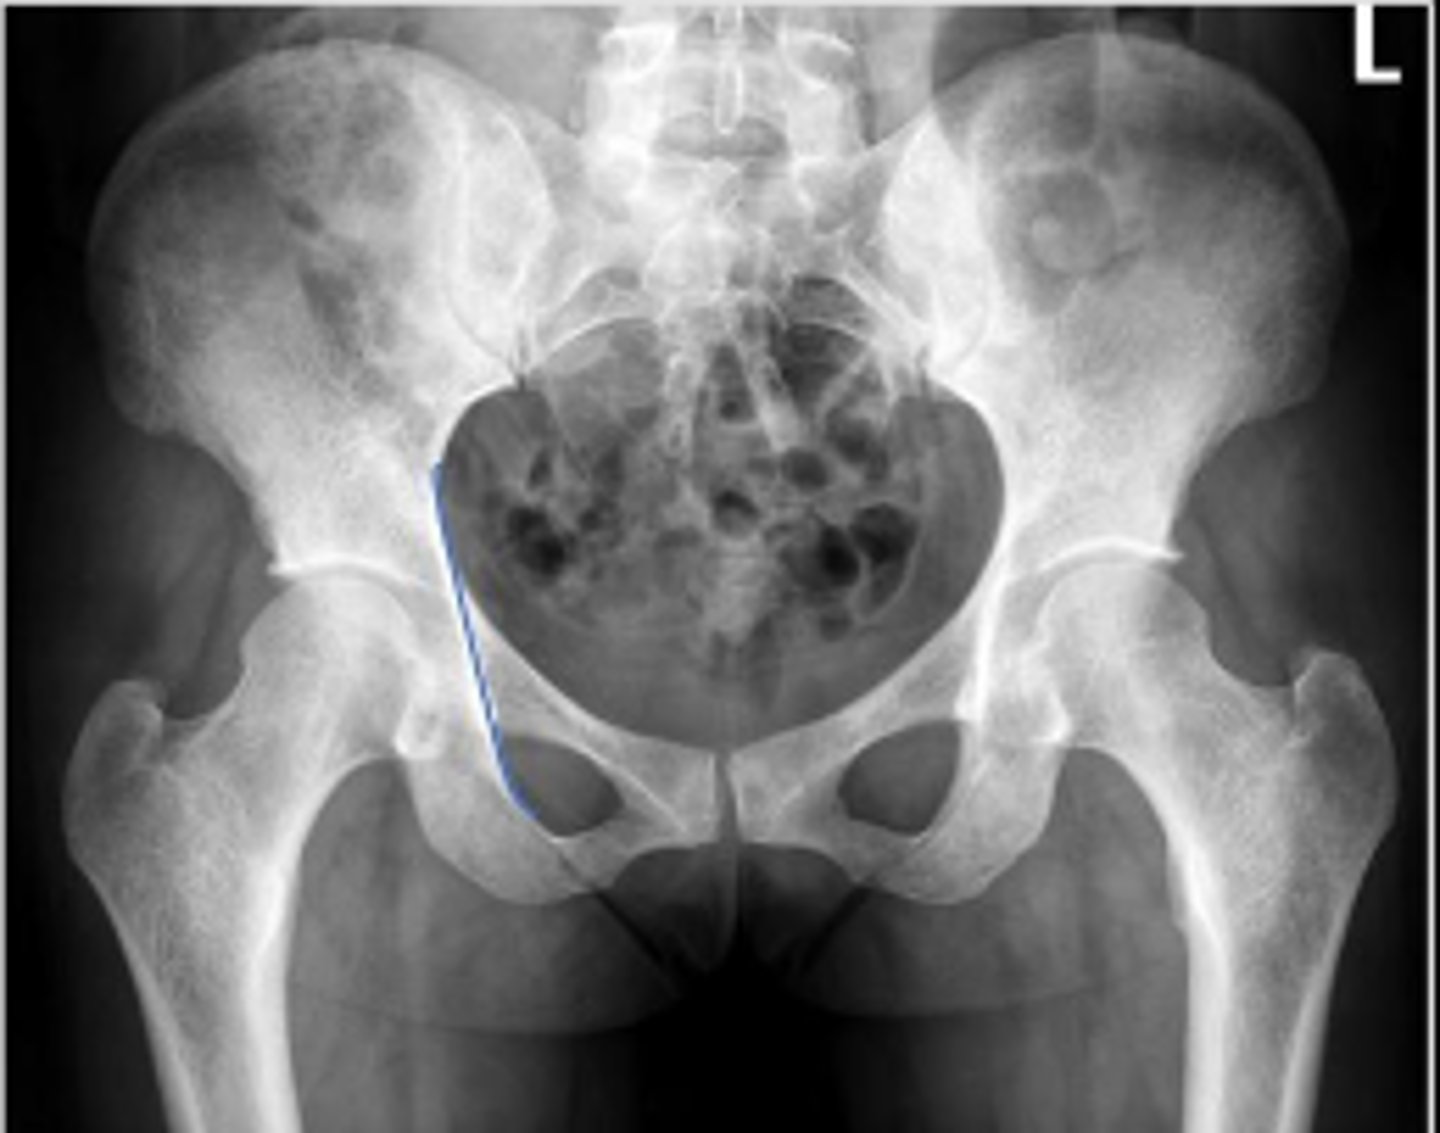

Bilateral frog leg view

What is the name of the radiographic view?

AP pelvis or bilateral hips

Name the radiographic view

Shenton's line

What is the name of the assessment?

From the undersurface of the femoral neck

continued to the inferior aspect of the superior

pubic ramus

What are the osseous land marks for this assessment?

Hip dislocation, fracture

Name 2 conditions that may result in an abnormal assessment?

Posterior hip dislocation

What is most significant radiographic finding?